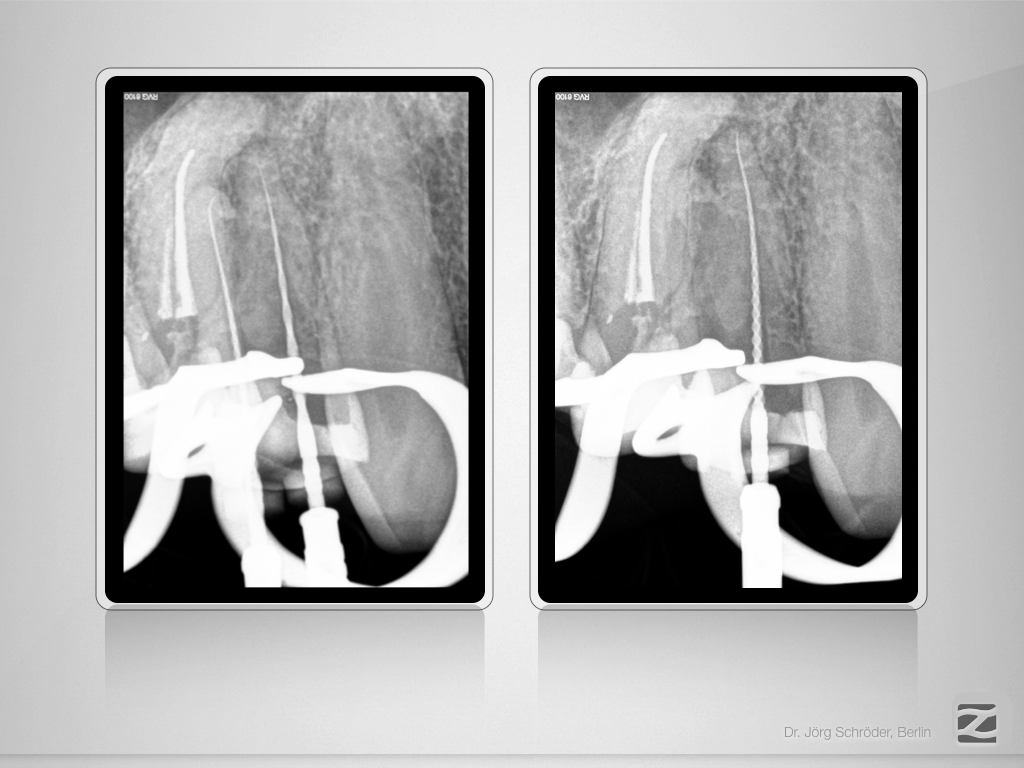

14 & 15 D.004

Unvollendete